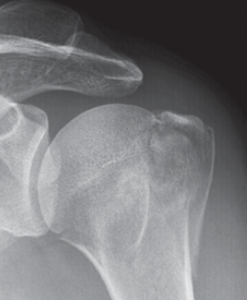

Oberarmkopfnekrose